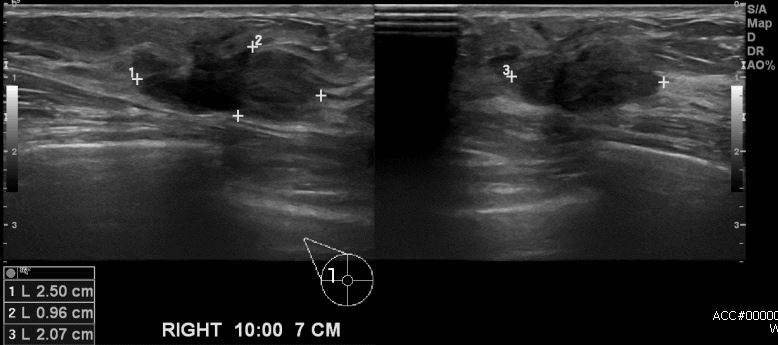

우측 유방에 만져지는 멍우리로 내원하신  50대 여성분으로 우측 10시 방향에서 7cm

떨어진 거리의 혹 조직검사 시행하여 우측 침윤성 유관암 진단되었습니다.